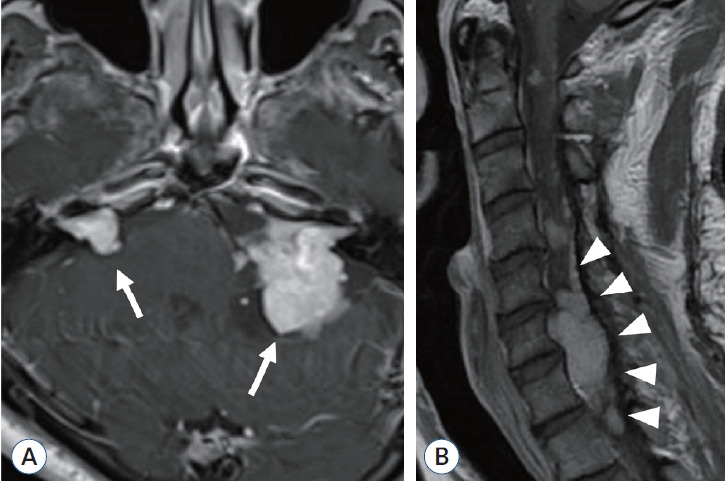

2型神经纤维瘤病(NF2)是一种常染色体显性遗传病,以双侧前庭神经鞘瘤和其他中枢神经肿瘤如脑膜瘤和脊髓室管膜瘤为特征。症状根据诊断时的年龄和肿瘤的位置而有所不同。NF2的诊断标准已定期修订,并于2022年更新了新的命名法“NF2相关神经鞘瘤病”,以区分NF2与其他神经鞘瘤易感性疾病,如SMARCB1-、LZTR1-和22q相关神经鞘瘤病。除了临床特征外,对这些基因的致病变异进行基因检测成为支持NF2和其他神经鞘瘤病(包括花叶病)诊断的重要本质。

Neurofibromatosis type 2 (NF2) is an autosomal dominant disease characterized by bilateral vestibular schwannomas and other central nervous tumors such as meningiomas and spinal ependymomas. Symptoms vary according to the age at diagnosis and the location of these tumors. The diagnostic criteria of NF2 have been regularly revised and recently updated in 2022 with a new nomenclature "NF2-related schwannomatosis" to differentiate NF2 from other schwannoma predisposing disorders, such as SMARCB1 (SWI/SNF-related, matrix-associated, actin-dependent regulator of chromatin, subfamily b, member 1)-, LZTR1 (leucine zipper-like transcription regulator 1)-, and 22q-related schwannomatosis. Addition to the clinical features, genetic testing for pathogenic variants in these genes became an important essence to support diagnosis of NF2 and other schwannomatosis, including mosaic conditions.